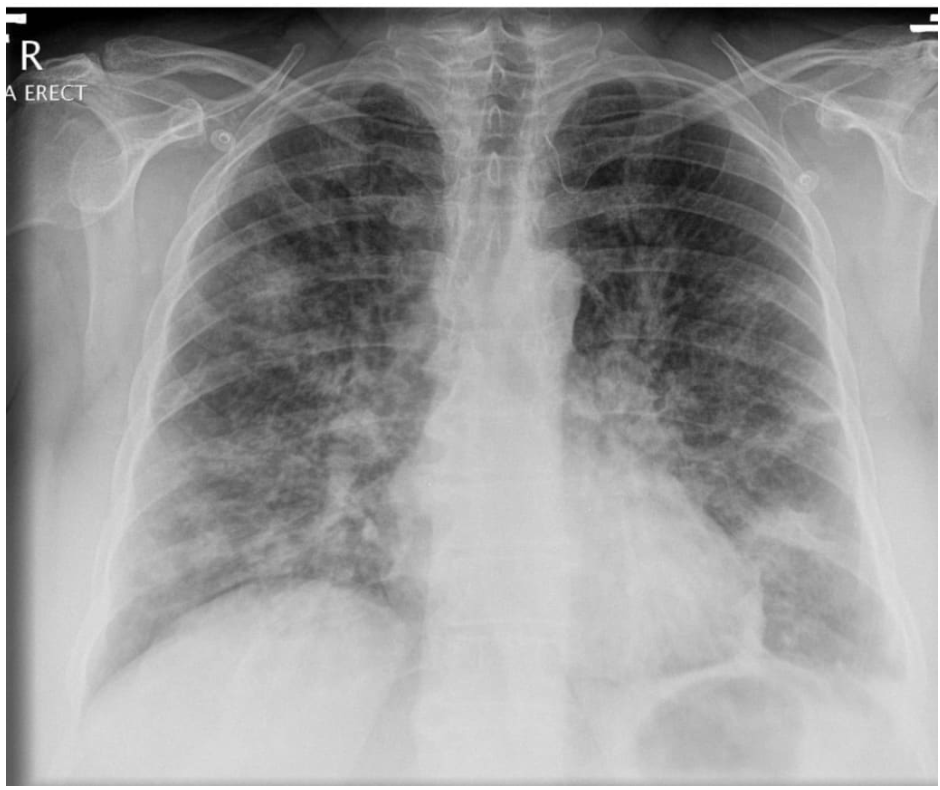

What pathology is shown on this chest x-ray?

= G ) Pulmonary oedema